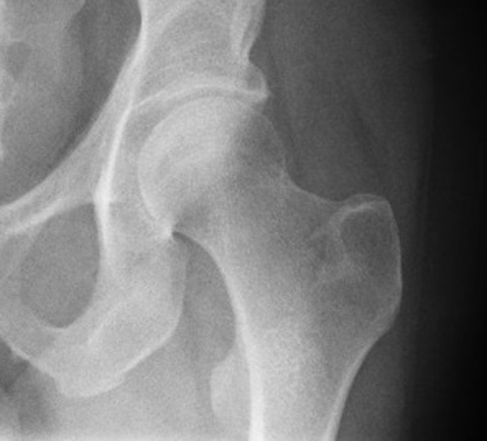

РОЗПІЗНАЙТЕ КІСТКУ. ПЕРЕЛОМ ЯКОЇ ЇЇ ЧАСТИНИ ВИ БАЧИТЕ НА РЕНТГЕНОГРАМІ?

варіанти відповідей

ULNA

RADIUS

FEMUR, ШИЙКА

ПРОКСИМАЛЬНОГО ЕПІФІЗА

ДИСТАЛЬНОГО ЕПІФІЗА

ДІАФІЗА

ЛІКТЬОВОГО ВІДРОСТКА

ПРОМЕНЕВОГО ВІДРОСТКА

НЕОПЕРОВАНИЙ ПЕРЕЛОМ ЦІЄЇ КІСТКИ І В ЦЬОМУ МІСЦІ ПРИЗВЕДЕ ДО СМЕРТІ В СЕРЕДНЬОМУ ЧЕРЕЗ КІЛЬКА РОКІВ. А ЦІ РОКИ ПЕРЕТВОРЯТЬСЯ НА СИДЯЧІ АБО ЛЕЖАЧІ МУКИ. ЯКОЇ КІСТКИ І ЯКОЇ ЇЇ ЧАСТИНИ?

HUMERUS, ХІРУРГІЧНА ШИЙКА

ВЕРХНЬОГО ДІАФІЗА

ULNA, ШИЙКА

HUMERUS, ШИЙКА

RADIUS, ШИЙКА